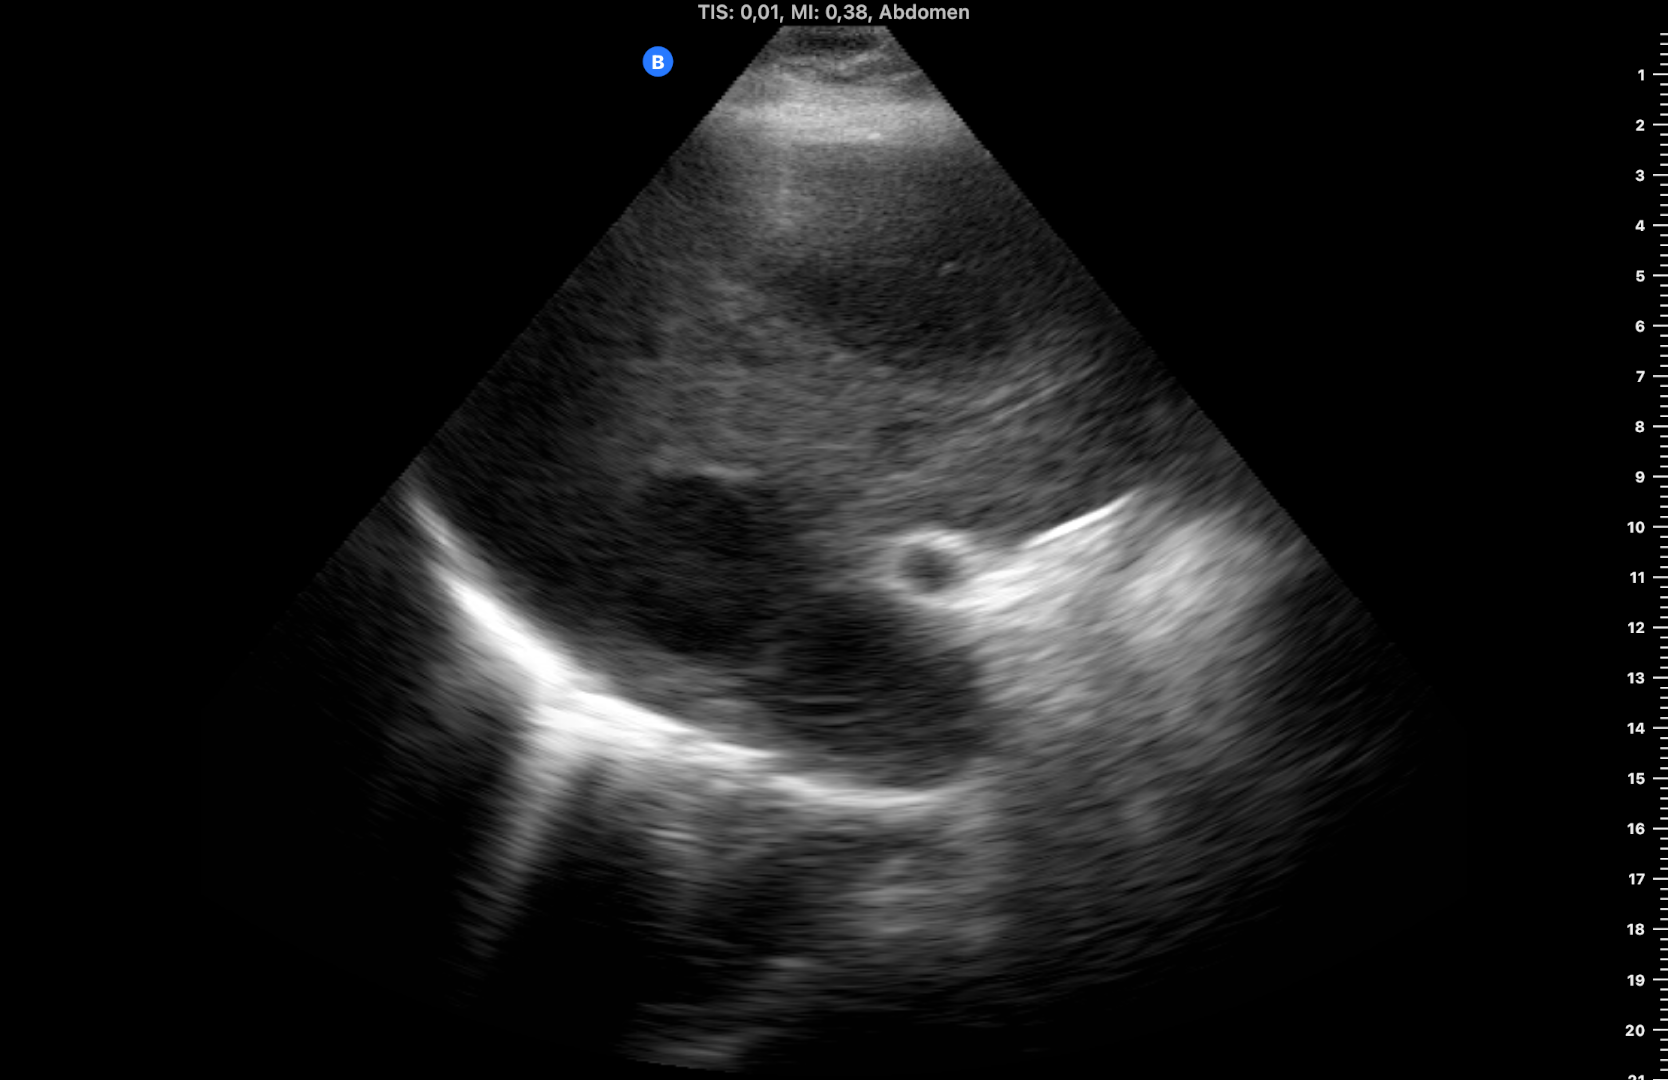

Ecografía inicial con ecógrafo portátil con múltiples LOES hepáticas hipoecogénicas de 5-6 cm de diámetro, alguna con centro hiperecogénico (figuras 1 y 2), que se confirman con ecógrafo de consola (figuras 3 y 4) con flujo Doppler aumentado respecto al resto de parénquima (hay vídeos).